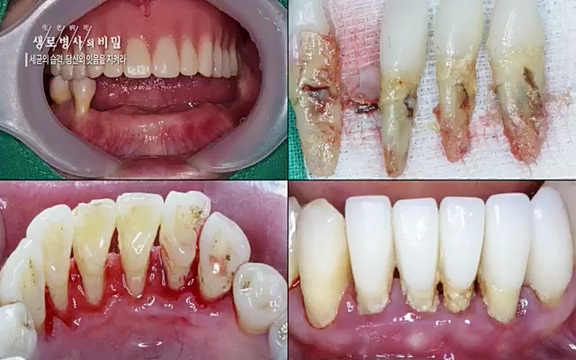

양승민 | 삼성서울병원 치주과 교수. 저희 제일 많이 알고 있는 치석이란 것들이 생기기 시작합니다

![[792회] 생로병사의 비밀 - KBS[세균의 습격, 당신의 잇몸을 지켜라!] 감기보다 병원을 더 자주 찾게 만드는 질병이 있다. 바로 치주질환이다. 2020년 외래 다빈도 질병 1위를 차지한 치은염 및 치주질환 환자는 1,637_20220505_140410.439.jpg](https://blog.kakaocdn.net/dn/bV7YZH/btrBhYM7pg2/A4jfhmO7kkR3VB78latMvk/img.jpg)

계승범 | 삼성서울병원 치주과 교수. 주로 저희가 플라크 (치태)라고 얘기하는 세균의 덩어리들이 문제가 됩니다.